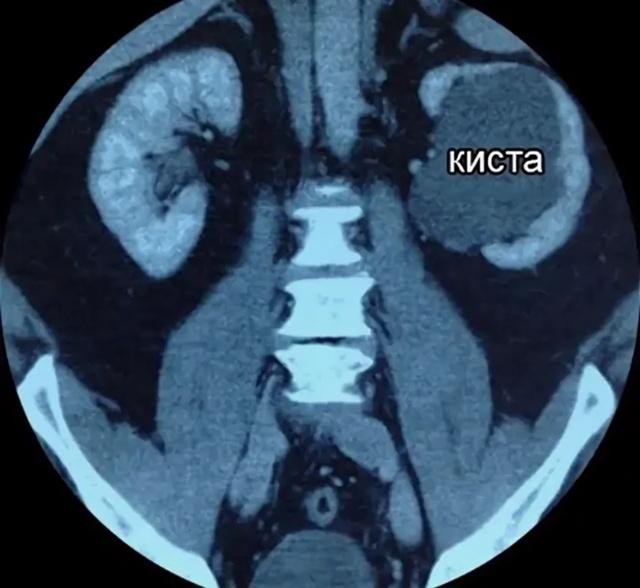

В отделении урологии № 1 Областной больницы им. Н.Н. Бурденко расширяют объем операций пациентам с кистами почек

В конце прошлой неделе специалистами 1-го урологического отделения Пензенской областной клинической больницы им. Н.Н. Бурденко проведена операция молодому пациенту с двумя синусными кистами почек, которые сдавливали с двух сторон мочевыводящие пути и сосуды почки, вызывая боли и нарушение функции. На операции хорошо видно, что мочеточник, почечная лоханка и почечная вена были непосредственно стенками кист», - поясняет к.м.н.  Михаил Миронов, заведующий отделением урологии № 1.

«Внутрисинусные кисты почек сдавливают ткани и сосуды органа, в результате чего происходят атрофические изменения, нарушается отток мочи и гемодинамические показатели. Хирургическому лечению подлежат все крупные, прогрессивно растущие кисты почек, не зависимо от их локализации. Операции выполняются по полису ОМС, для этого достаточно взят направление на госпитализацию в нашу больницу и не иметь противопоказаний.

«Для лечения заболевания в нашем отделении используются преимущественно малоинвазивные хирургические методы - лечение игольной аспирацией со склеротерапией под УЗИ наведением, лапароскопическая декортикация», - добавляет Михаил Анатольевич.